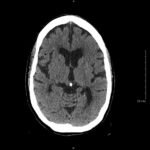

Non-contrast head computed tomography (CT) demonstrates multifocal bilateral hypodense lesions (white arrows) representing air emboli. Note the lesions are located in the intra-axial distribution which indicates an underlying vascular origin.

This event can arise in clinical and non-clinical settings and the diagnosis of cerebral air embolism should begin with clinical suspicion and evaluation. Most common causes include thoracentesis, hemodialysis, angiography, tissue biopsy, scuba diving, and central line or other vascular access procedures. Clinical signs of air embolism are broad depending on the affected system and include altered mental status, focal neurologic deficits in the distribution of the affected neurological region, cyanosis, hypoxia, hypercapnia, hypotension, wheezing, and bronchospasm.4 Recommended diagnostic imaging for cerebral air imaging includes CT and magnetic resonance imaging (MRI), but CT is most often performed first due to availability and the short duration of the test.5 The location of intracranial air emboli can be found in the intra-axial or extra-axial distribution and may indicate the possible etiology. Pneumocephalus is usually found in the extra-axial space most commonly after trauma or neurosurgery while air emboli are found in the intra-axial vascular distribution.6